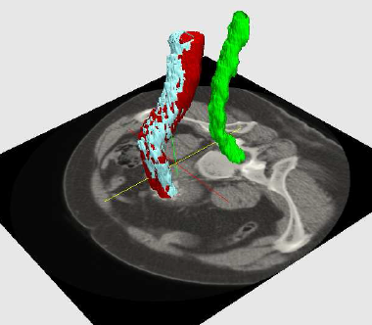

El segundo escenario de aplicación apuntado por el proyecto ALTAIR concierne al campo de la cirugía vascular, concretamente a la predicción de la evolución de un aneurisma de aorta abdominal excluido mediante el procedimiento EVAR (Endovascular Aneurysm Repair).

El AAA es una dilatación focal en algún punto de la sección abdominal de la aorta. Hoy en día una de las opciones de tratamiento preferenciales es un procedimiento quirúrgico mínimamente invasivo llamado Reparación Endovascular de Aneurisma (Endovascular Aneurysm Repair o EVAR) en el que se inserta una prótesis endovascular (stent graft) para excluir el aneurisma de la circulación sanguínea. La EVAR requiere un seguimiento post-tratamiento para asegurar que la endoprótesis es estable (ausencia de fugas o endoleaks –presencia de flujo sanguíneo dentro del saco aneurismático) y que dicho saco ha quedado debidamente excluido de la circulación. Este seguimiento se realiza mediante estudios de imágenes de CT realizados a intervalos regulares. Una reducción del tamaño del aneurisma indica que la exclusión ha sido efectiva, mientras que una expansión del mismo o la presencia de una fuga son indicadores de que el tratamiento ha fallado y existe riesgo de ruptura. Se ha observado que el tamaño de algunos aneurismas no varía o aumenta a pesar de haber sido adecuadamente tratados por vía endovascular. Aunque en ocasiones esto puede ocurrir por la presencia de una fuga, el saco puede seguir aumentando de tamaño sin la presencia de una fuga detectable, fenómeno que se conoce como endotensión y que ocurre en alrededor de un 36% de pacientes.

En este contexto, el proyecto ALTAIR tiene como segundo objetivo cuantificar el riesgo de ruptura del saco aneurismático tras ser intervenido mediante EVAR, utilizando un modelo de predicción basado en un conjunto de medidas o características físicas y de textura del saco. Se estudiará la textura del AAA a partir de imágenes CT del post-operatorio en varios instantes de tiempo para predecir su evolución y para localizar posibles casos con fugas no detectables mediante inspección visual. Esta parte del proyecto se realizará en colaboración con Hospital Universitario de Donostia.